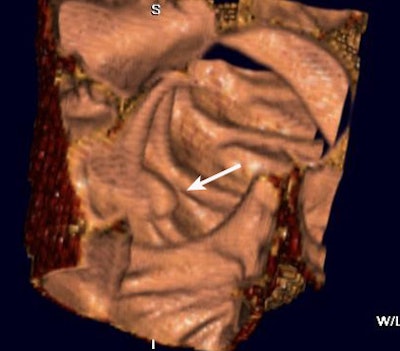

| A colonoscopically and pathologically proven 6- to 9-mm polyp in the transverse colon cannot be seen, even in retrospect, due to technical error. Above, representative axial image shows excellent preparation and distension of the transverse colon. On both the prospective and retrospective interpretation, no lesion could be identified in the transverse colon. Below, coronal reformation of the transverse colon shows good distension and good preparation. There is some motion artifact (arrows) from breathing which minimally obscures a portion of the transverse colon. |

There were 15 technical errors, and in seven of the 15 the lesion could not be identified retrospectively despite excellent bowel prep and good distension. Of these, he said, four were flat lesions, and three were located on a fold. Other technically challenging cases were complicated by the presence of stool or fluid in the involved segment, or by failure to achieve good distension in the involved segment. A breathing artifact prevented visualization of an 8-mm polyp in one patient.